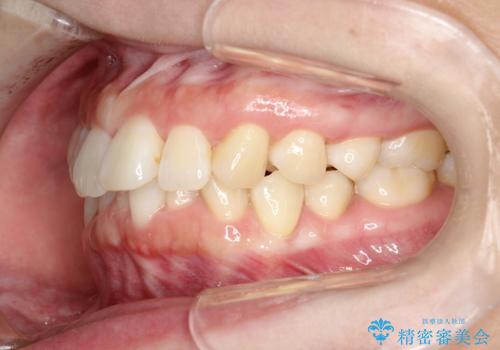

インビザライン ライトパッケージによる部分矯正治療 下の前歯のみの歯並び改善

- インビザライン ライトパッケージパーシャル(下顎のみ)

- 下の前歯の歯並びのみの改善をご希望されました。

インビザライン ライトパッケージ下顎のみ(1枚~14枚まで)での治療を行なっていきました。

マウスピース枚数 初回14枚 + 追加13枚

概ね7ヶ月で治療完了しました。

インビザラインのライトパッケージでは14枚までという枚数制限がありますが、限られた枚数の中で当院独自の工夫を随所に盛り込み、狙い通りの治療結果が得られました。